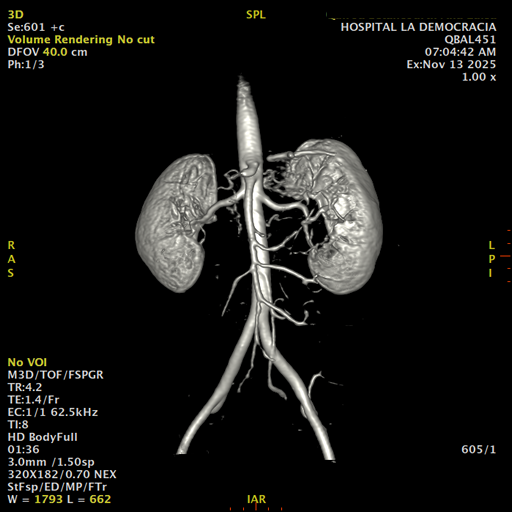

Se prepara a paciente para ingreso a zona 4 del área de resonancia. Se coloca a paciente en decúbito supino, se canaliza en vena antecubital, se utiliza bobina de abdomen de 16 canales, se adquieren localizadores en tres planos, luego se procede a adquirir imágenes en diferentes planos, con secuencias echo spin y eco de gradiente, potenciadas a T1 y a T2.

Los sistemas colectores del riñón derecho y del riñón izquierdo, muestran alteración de sus calices primarios y secundarios, mostrando dilatación, la pelvis renal y el uréter se observan de características normales lo que indica que no hay proceso obstructivo.

Se observa dilatación del sistema calicial sin proceso obstructivo compatible con una anormalidad del desarrollo de los sistemas colectores de ambos riñones, definiéndose como una “megacaliosis”